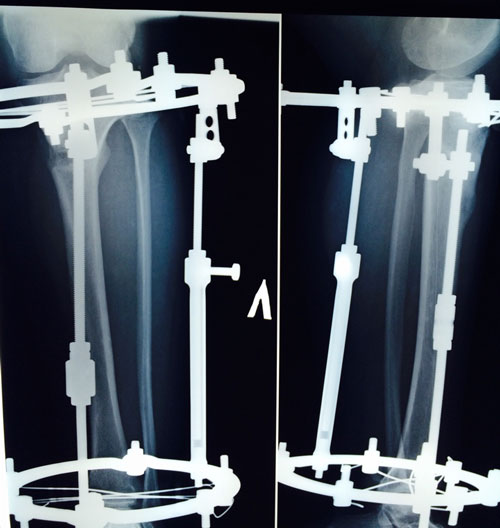

Диагноз: ахондроплазия, варусная деформация обеих голеней 155 градусов.

Дата операции 08.07.2015г.

Исходник.